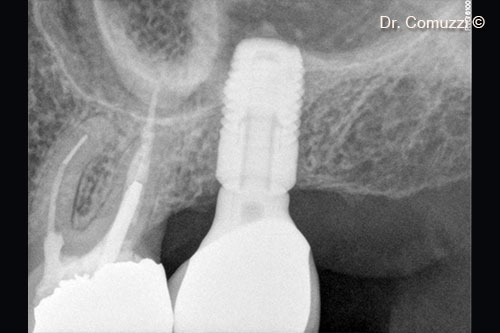

4. Implant insertion (Astra, 9-mm length and 5-mm diameter)

6. X-ray of Sinus Lift at implant placement